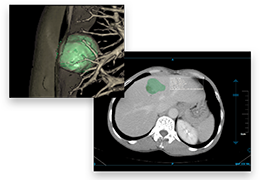

成像智能。

Eclipse 成像智能功能提供强大的处理能力和最佳质量的影像,同时减少质量错误并提高剂量效率。

凭借 AI、专有算法和先进的影像处理能力,提供出色的影像质量和无与伦比的诊断信心。

与标准影像处理相比,智能降噪功能可使客户降低辐射剂量,而不会损失影像质量。这在新生儿和儿科成像中尤其重要,在这种情况下以尽可能低的剂量成像至关重要。

提供相配视图选项,以减少所需的曝光次数,并提供更清晰的感兴趣区域视图。